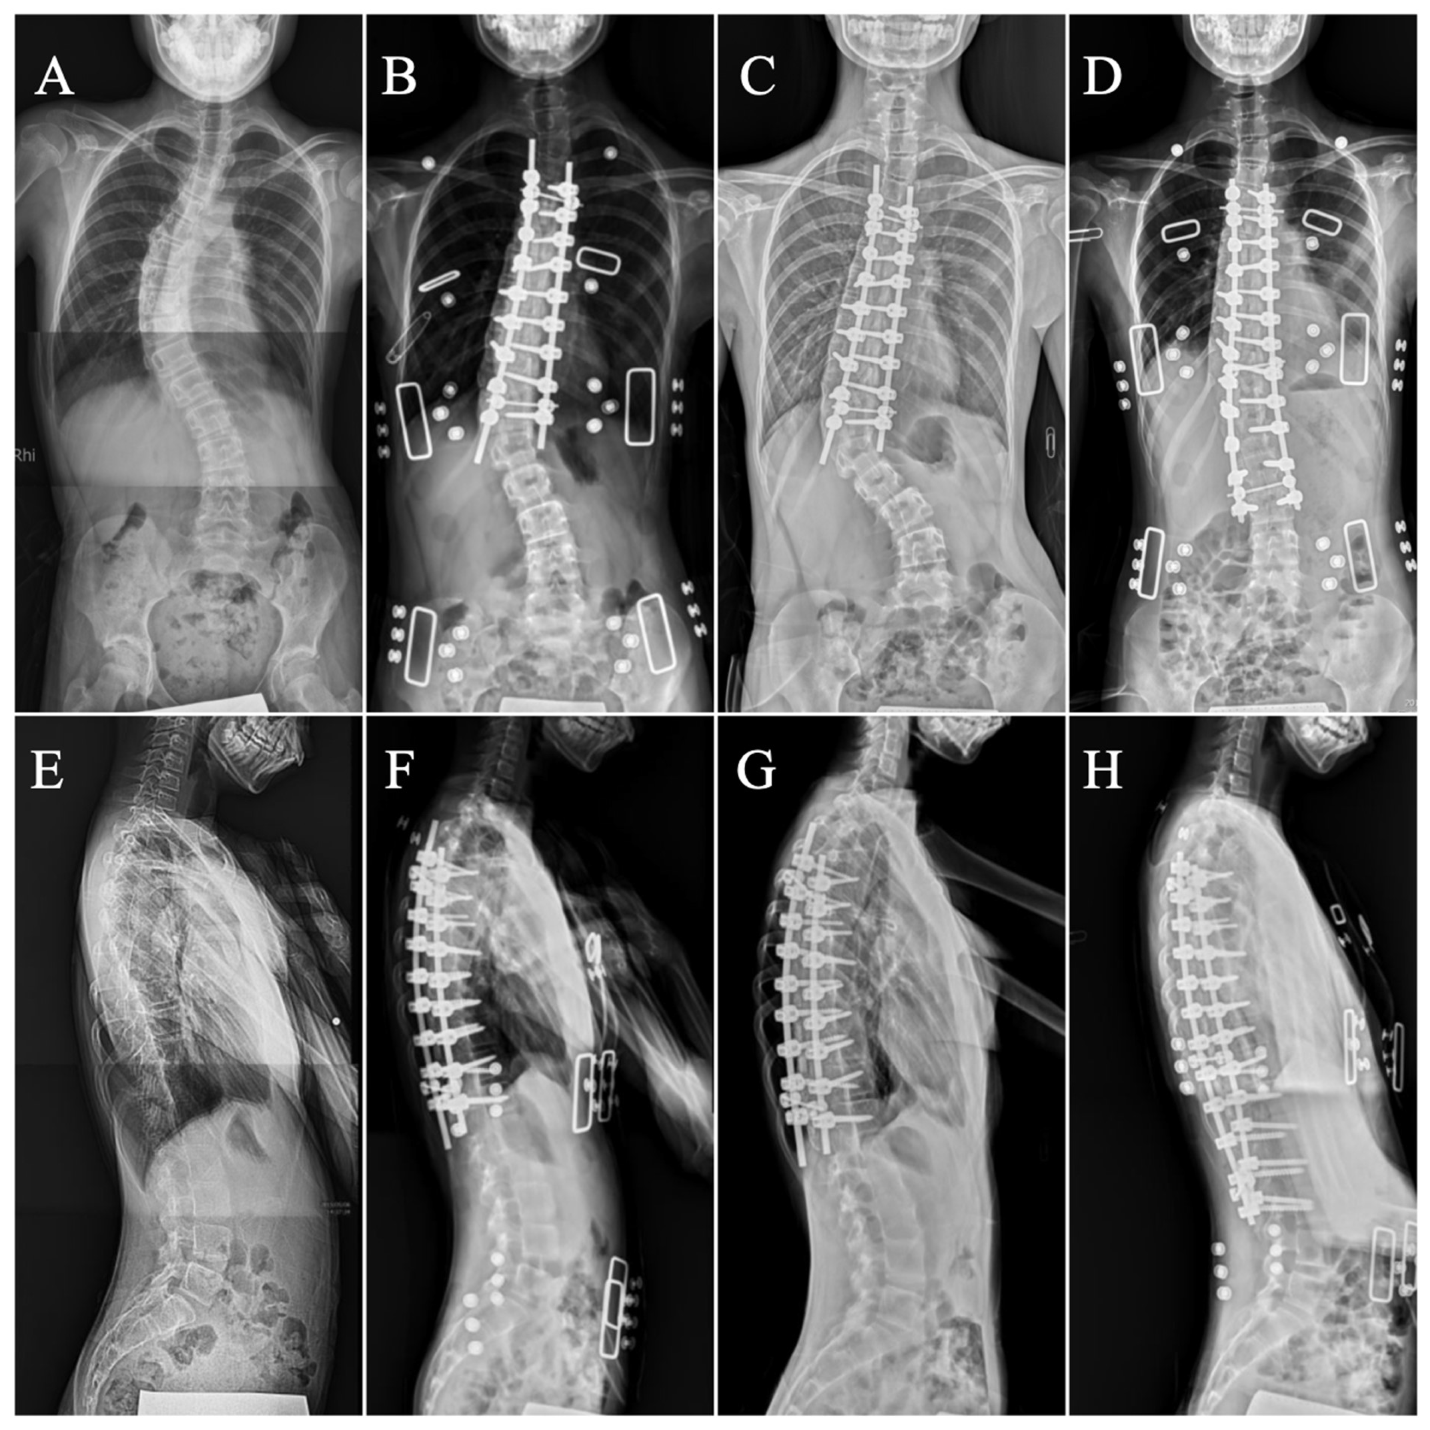

Navigation-Assisted One-Staged Posterior Spinal Fusion Using Pedicle Screw Instrumentation in Adolescent Idiopathic Scoliosis—A Case Series

2.4. Surgical Procedure and Postoperative Care

2.5. Measurements